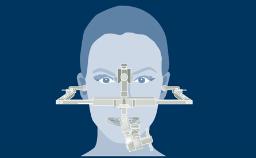

A thorough patient assessment is the basis of any dental treatment plan that may or may not include implants. It is directly related to the treatment outcome.

This ITI Academy module serves as an overview and introduction to the related modules that will discuss each of the components involved in structured patient assessment and treatment planning in detail.

- list the main components of a structured patient assessment and treatment planning protocol in their proper sequence